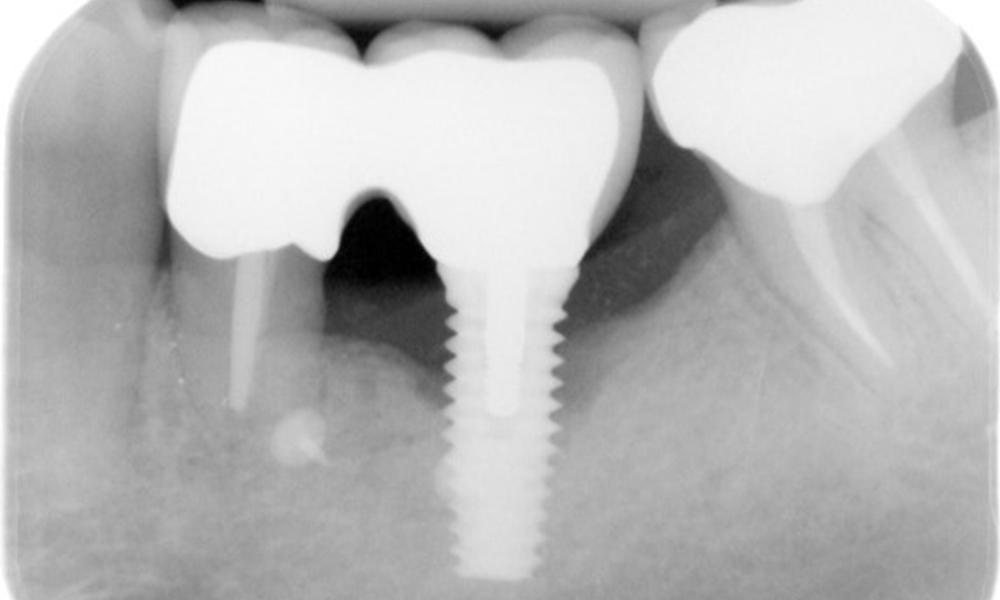

В историята на заболяването на пациента няма особени рискови фактори със специфични дентални последици. Следователно ключовият фактор е изискването по отношение на оралното здраве. В това отношение има данни за дълбочина на сондиране от 5 mm при импланта в 3-ти квадрант, а на рентгеновата снимка - за увеличена костна загуба. Пациентът също така има стабилно понастоящем пародонтално заболяване и две активни начални кариозни лезии.